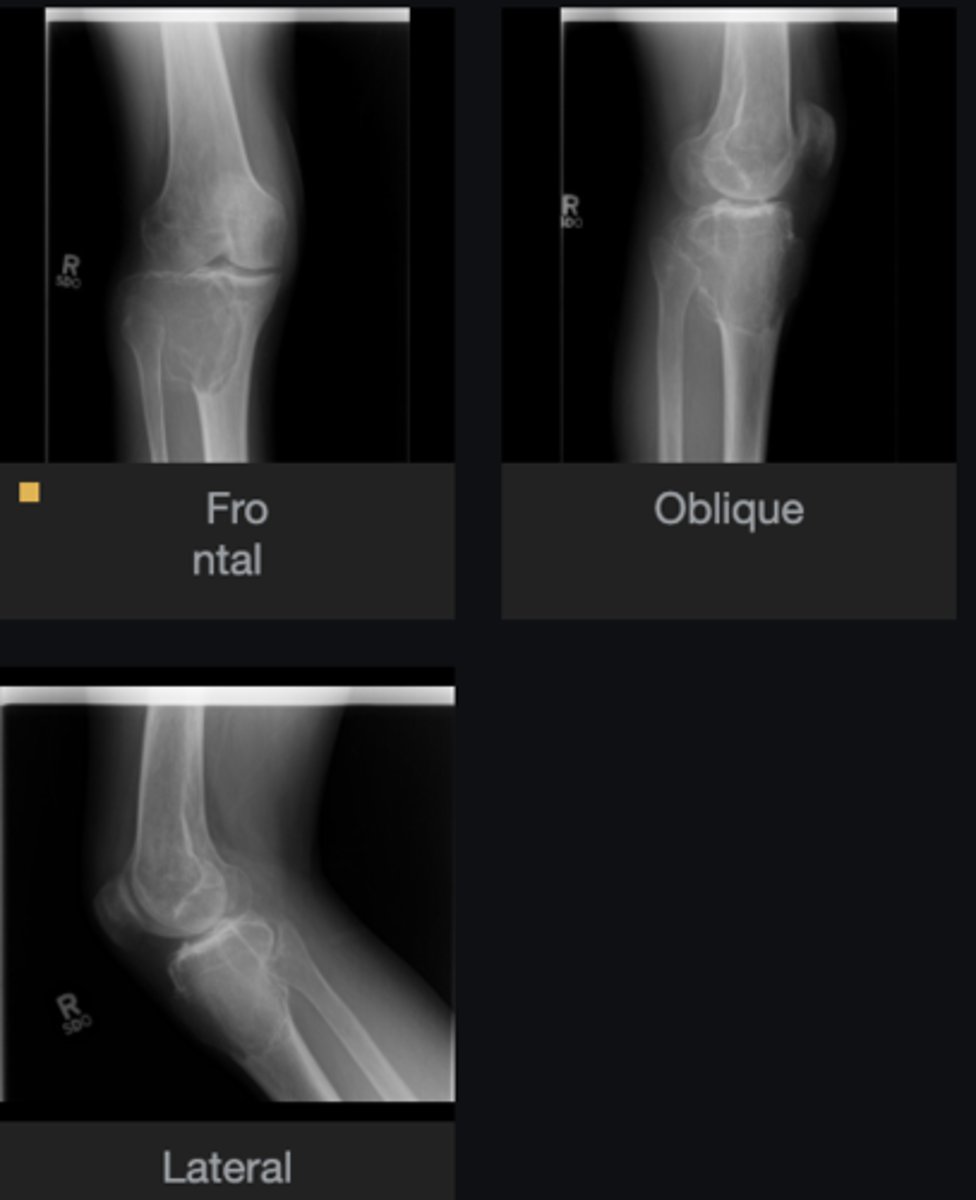

Lateral proximal tibia

Bone

<p>Bone</p>

- Longitudinal: epiphysis/metaphysis (up to joint surface)

- Eccentricity: eccentric

- Transverse: medullary

Location

<p>Location</p>

Monostotic

Mono/polyostotic

<p>Mono/polyostotic</p>

New cards

>1 cm

Size

<p>Size</p>

- Lytic

- Geographic

- Short zone of transition

Behavior

<p>Behavior</p>

- Cortical thinning

- Cortical expansion

Cortex

<p>Cortex</p>

Giant cell tumor

Most likely diagnosis?

<p>Most likely diagnosis?</p>

Refer to orthopedist or oncologist

Next step?

<p>Next step?</p>

Could be aggressive (20%)

Concerns/complications?

<p>Concerns/complications?</p>